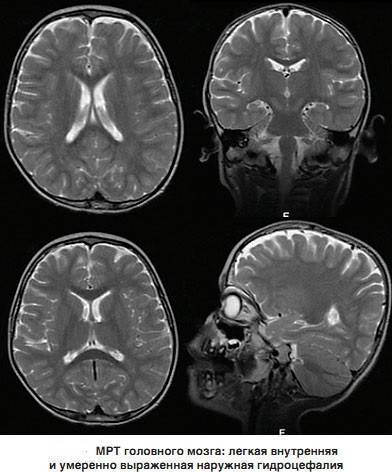

Признаки умеренно выраженной наружная

Признаки умеренно выраженной наружная 113 фото